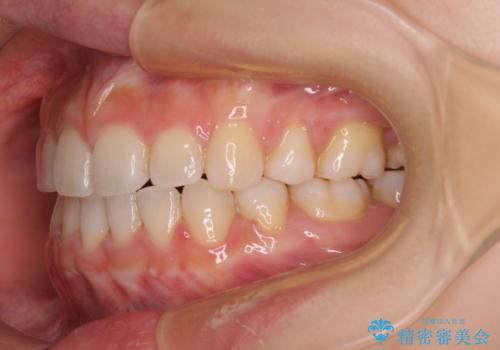

- 前歯が突出しているために口が閉じられないとのことで来院された患者様です。

上下ともに顎が小さく、歯列が前方に突き出していたため、上下左右の第一小臼歯4本を抜歯し、口元の突出感を改善していくこととしました。

口元の突出感が改善されると睡眠中の口呼吸が予防でき、鼻炎などの疾患予防に繋がると言われています。